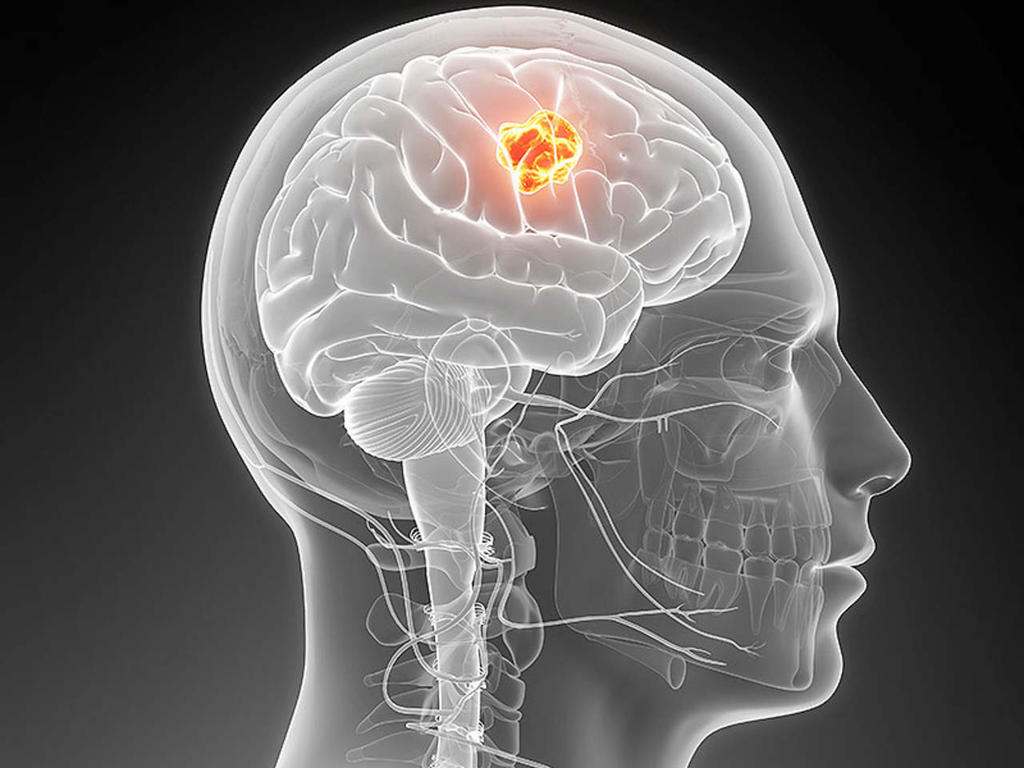

OBJETIVO: TUMORES CEREBRALES

El primer objetivo de este equipo de físicos, médicos, biotecnólogos y matemáticos es atacar con los microrrobots los tumores cerebrales, que son "particularmente difíciles" de tratar con la tecnología actual, ya que la radiación y la cirugía en la cabeza pueden causar daños severos e irreversibles.

Ahí entra el avance científico de Bionaut Labs: ser capaces de administrar medicamentos directamente en el tumor, sin afectar a cualquier otra parte del cerebro.

Para el inicio de su andadura, Shpigelmacher, formado en física, matemáticas, finanzas y ciencias de la computación, y su equipo decidieron enfocarse en el tratamiento de gliomas del tronco encefálico, un tumor pediátrico "incurable".